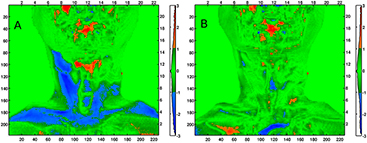

3.4. Applicability of the method to a clinical dataset

Qualitative assessment of the pCT to CBCT DIR for the patient case revealed no major discrepancy between the vCTCBCT and the CBCT. In particular, figure 10 presents results of the WET comparison using the gamma evaluation using criterion of 3 mm / 2 mm WET. We observed that the percentage of pixels passing the gamma comparison to the rpCTCBCT is increased when using the vCTCBCT (94%) instead of the pCTCBCT (77%). The mean WET differences were −0.6 mm ± 3.2 mm and 1.1 mm ± 3.6 mm respectively. The large neck portion failing the gamma evaluation for the pCTCBCT versus rpCTCBCT suggests that a beam coming from the left in figure 10 would suffer from range uncertainty, which could be reduced by employing the vCTCBCT. A detailed analysis of DIR accuracy for clinical datasets is beyond the scope of this paper and will be investigated in a follow up study using rpCT scans as reference.

Figure 10. (a) Result of the gamma comparison of WET using criteria 3 mm / 2 mm WET of the pCTCBCT versus the rpCTCBCT (WETpCT–WETrpCT). (b) Comparison of the vCTCBCT to the rpCTCBCT (WETvCT–WETrpCT). The left and bottom axis are in pixels while the top and right axis are in cm. The colorbar serves as a histogram of the gamma index distribution.

Following the encouraging phantom results, in this work we have also applied our algorithm on a single patient case containing the data described above. We observed that the algorithm we tested on phantom data performed well on patient data. This supports further, thorough investigation of the method using several clinical datasets containing replanning CT and CBCT images, which is currently underway.

A limitation of our study is that our phantom fails to fully reproduce the range of patient size observed in H & N CT images. In H & N cancer cases adjuvant PTVs covering lymph nodes can extend into the upper thorax. In that region two issues are observed in CBCT images: i) a decrease of soft tissue CT number intensity due to increased beam hardening, scattering and attenuation from the shoulders and ii) truncation of the shoulders in the CBCT images due to the smaller FOV. Our initial patient results suggest that CT numbers on the vCT were not degraded by issue i). The use of an anterior beam to cover the region suffering from lateral truncation would also limit the impact of issue ii).